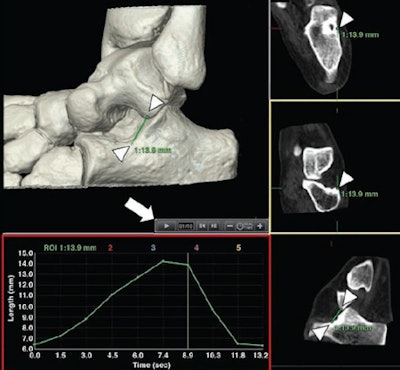

Postprocessing tool user interface. Software allows positioning of various reference markers in any bony structure of study area (arrowheads). Time controls (arrow) allow visualization of all available volumes of dynamic acquisition. Once reference markers for distances (green lines) or angles (not shown) are set, software automatically projects them to all volumes acquired. After analysis, variation of measurement performed in acquisition volumes is displayed graphically (red rectangle). Data can also be exported for further analysis. All images republished with permission from AJR."With dynamic CT, the subtalar joint is sampled at various times during a given maneuver," Teixeira and colleagues wrote. "Thus, a large amount of data is available for analysis, and the study of measurement variations during motion, as opposed to comparisons between pre- and poststress acquisitions, is possible. This capability increases the potential to identify fine talocalcaneal positional anomalies."